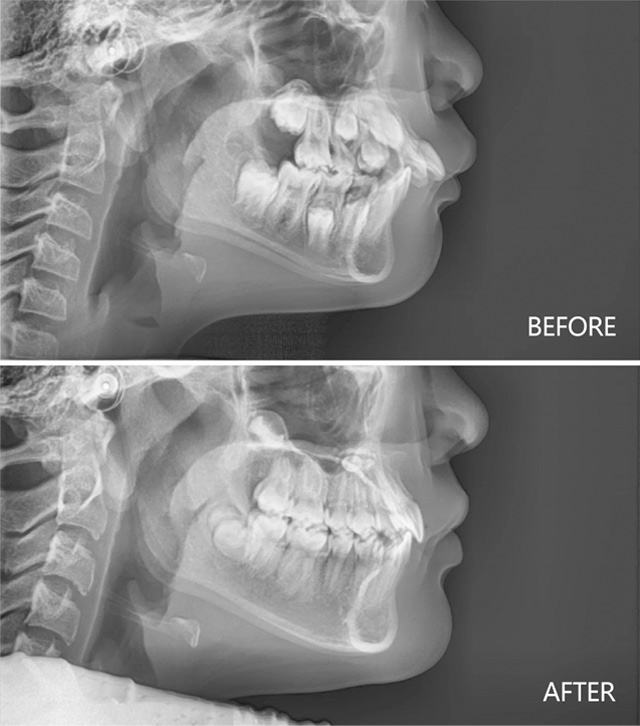

下巴后缩合并深覆盖治疗前后

9岁女孩下巴后缩治疗前后

8岁男孩下巴后缩治疗前后